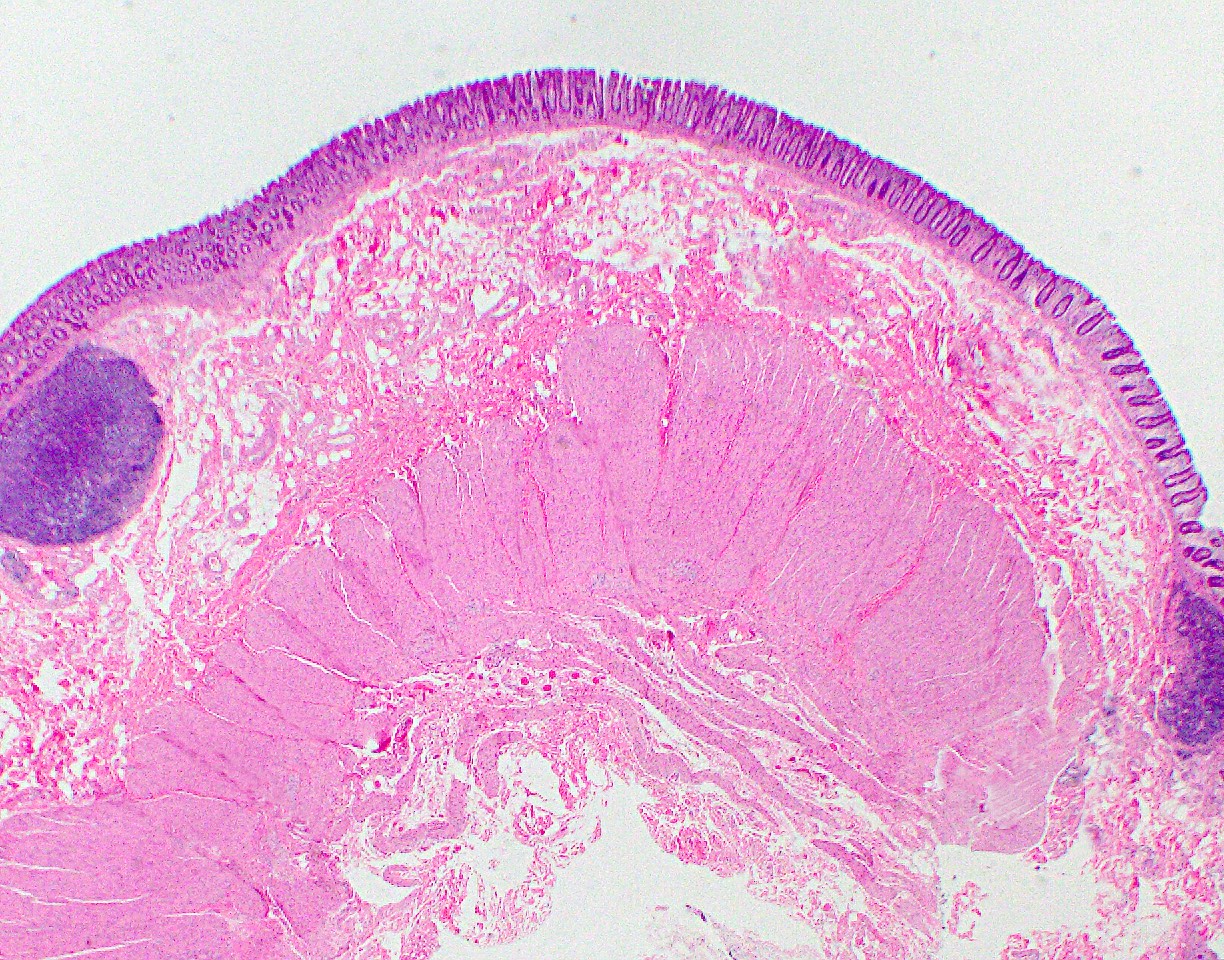

Microscopic (histologic) images

Microscopic (histologic) description

- Mucosa is composed of the epithelium, lamina propria and muscularis mucosa

- As the epithelium invaginates into the underlying lamina propria, it forms glandular structures called crypts, arranged in a characteristic parallel test tube-like pattern

- Muscularis mucosa:

- Muscularis mucosa consists of thin strands of smooth muscle fibers separating the mucosa and submucosa

- Submucosa:

- Consists of loose connective tissue, thin smooth muscle bundles, nerve plexuses (Meissner plexus and Henle deep submucosal plexus) with ganglion cells, stromal cells, adipose tissue and vasculature

- Muscularis propria:

- Consists of inner circular layer and outer longitudinal layer and Auerbach nerve plexus in between the 2 muscle layers

- Subserosa and serosa: subserosa is composed of fibroadipose tissue and is covered by the serosa lined by cuboidal mesothelial cells